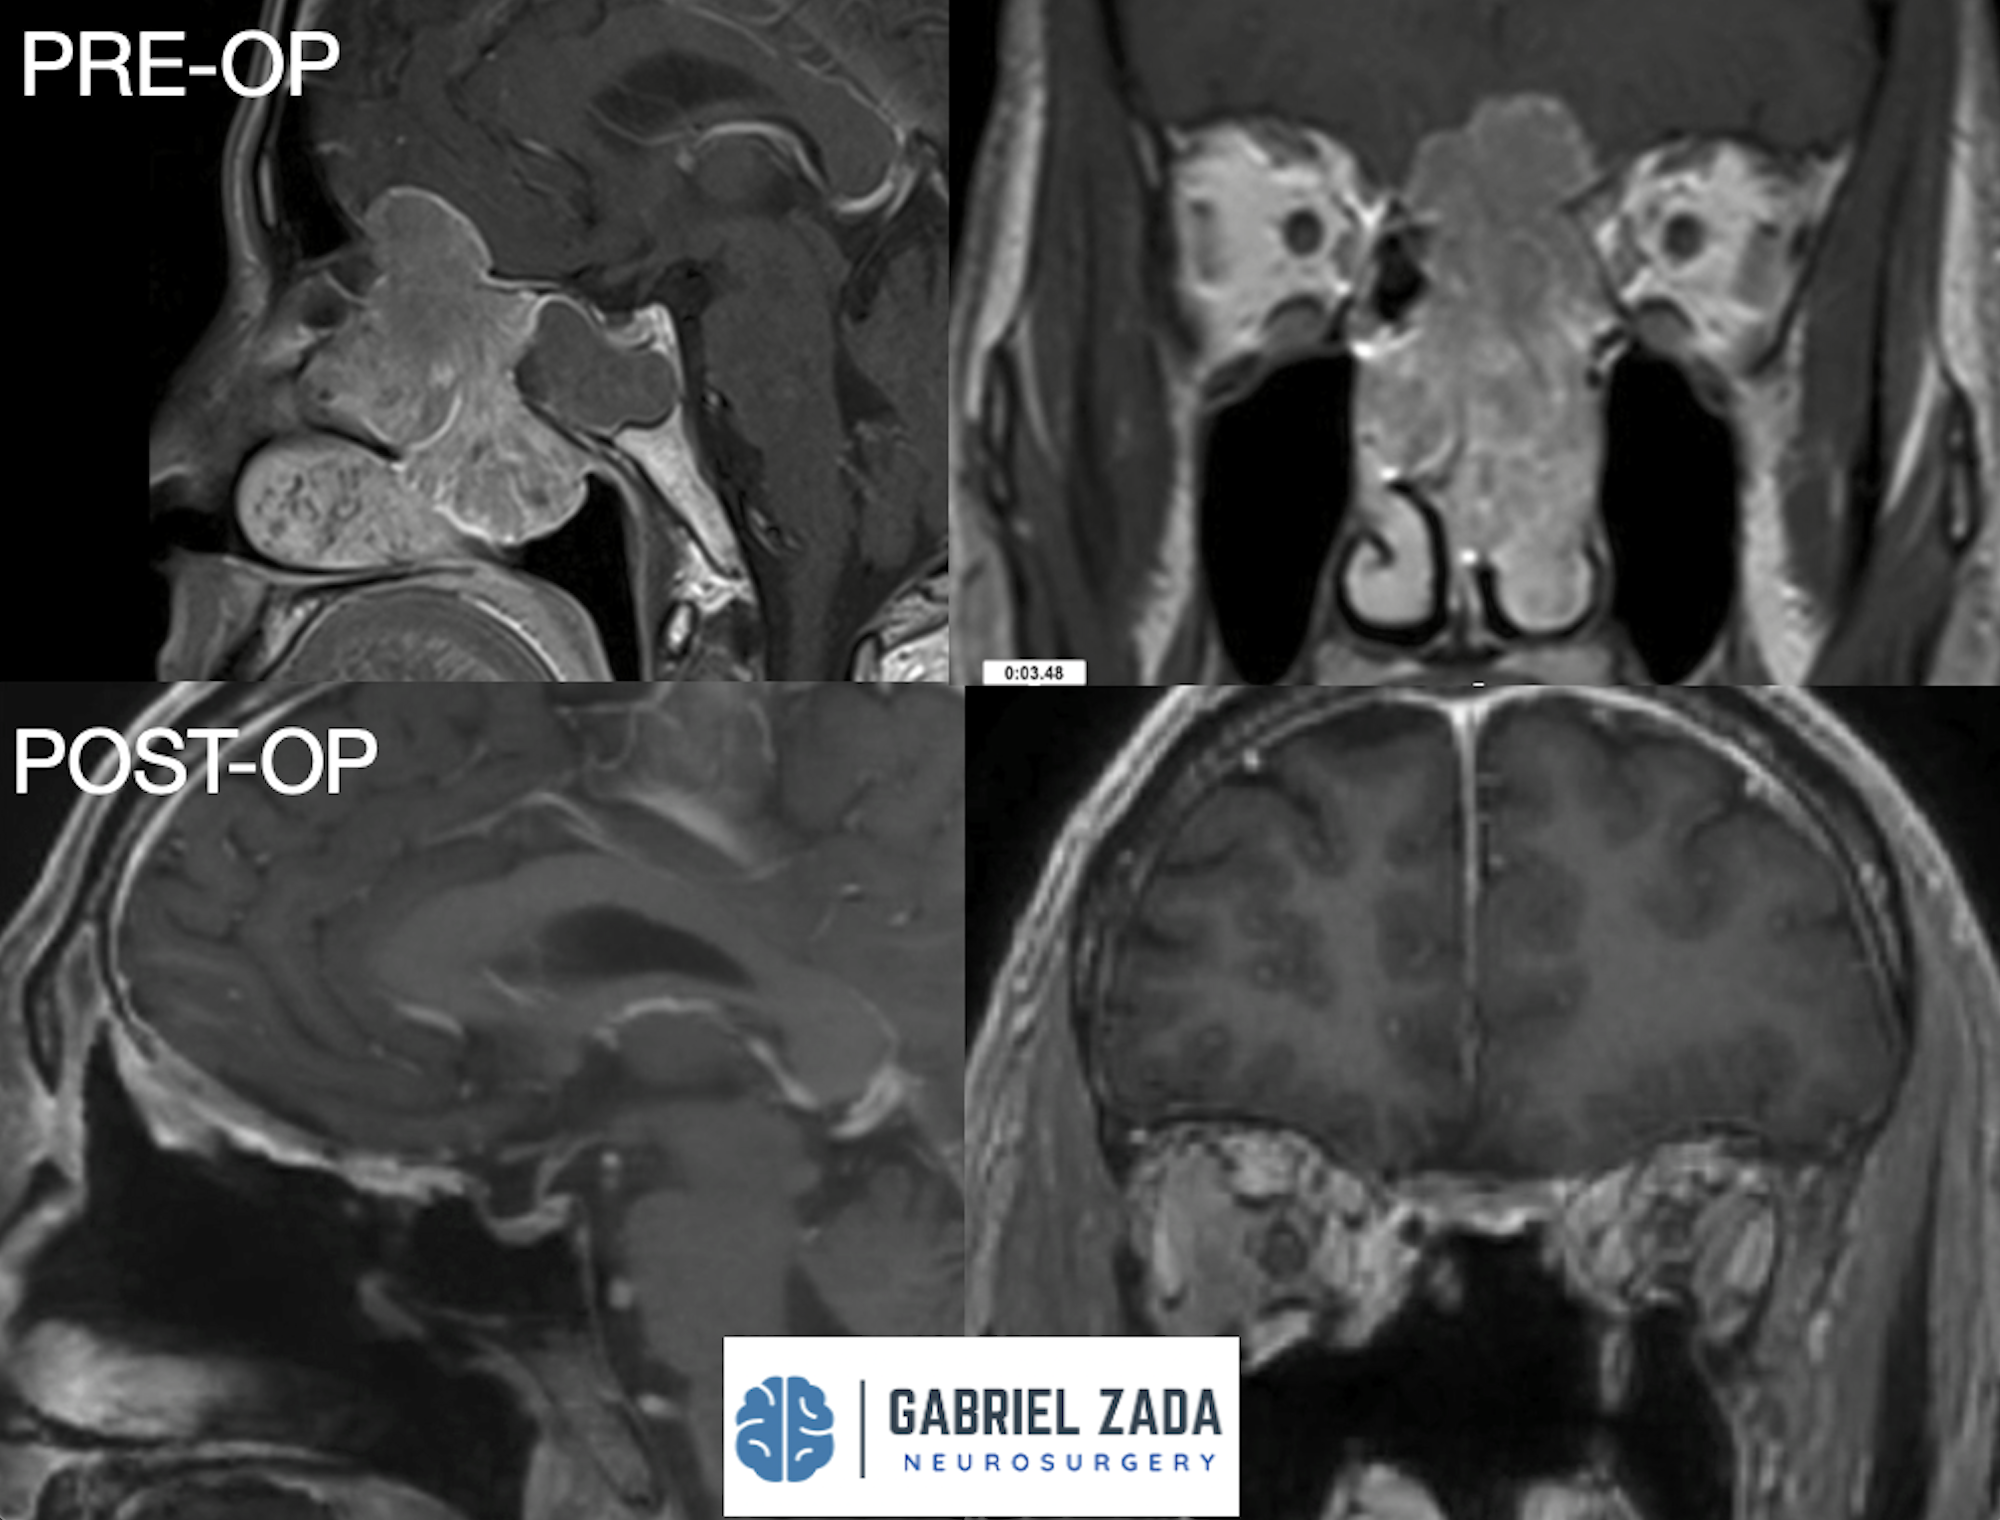

Explore this comprehensive gallery featuring pre‑ and post‑operative imaging of patients with skull‑base tumors treated by Gabriel Zada, MD, MS, FAANS, FACS. These cases highlight Dr. Zada’s expertise in advanced neurosurgical techniques and outcomes.

*Representative cases shown for educational purposes. All images de-identified. Individual results vary.